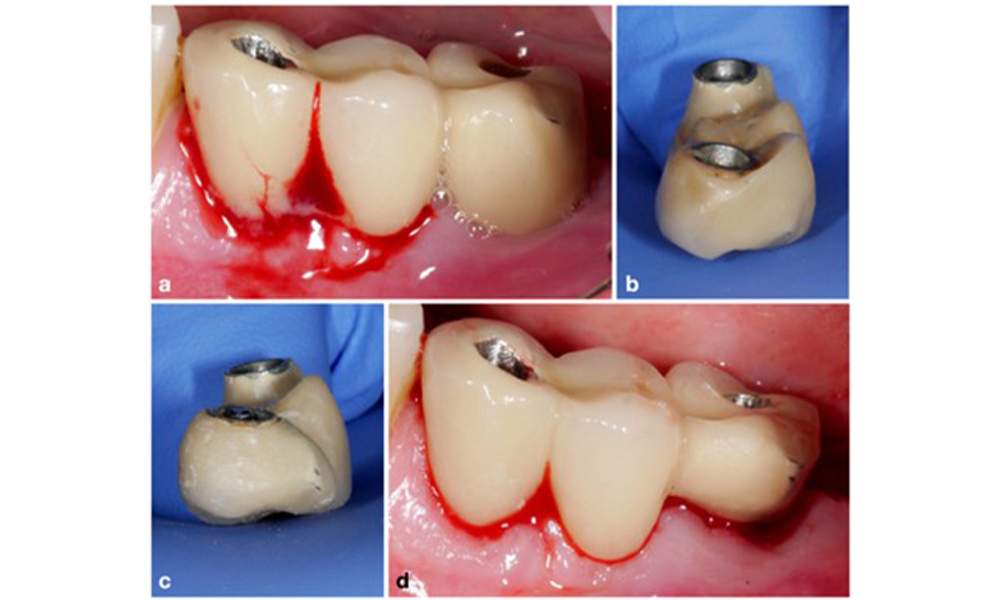

Modification d'un bridge existant. Si la restauration empêche de prendre des mesures d'hygiène bucco-dentaire suffisantes (remarquez le dépassement extrême sur la face buccale de la molaire) (a-b), l'une des premières étapes du traitement doit consister à ajuster la conception de la prothèse pour permettre un nettoyage efficace (c-d).

Figure 5. Modification d'un bridge existant. Si la restauration empêche de prendre des mesures d'hygiène bucco-dentaire suffisantes (remarquez le dépassement extrême sur la face buccale de la molaire) (a-b), l'une des premières étapes du traitement doit consister à ajuster la conception de la prothèse pour permettre un nettoyage efficace (c-d).